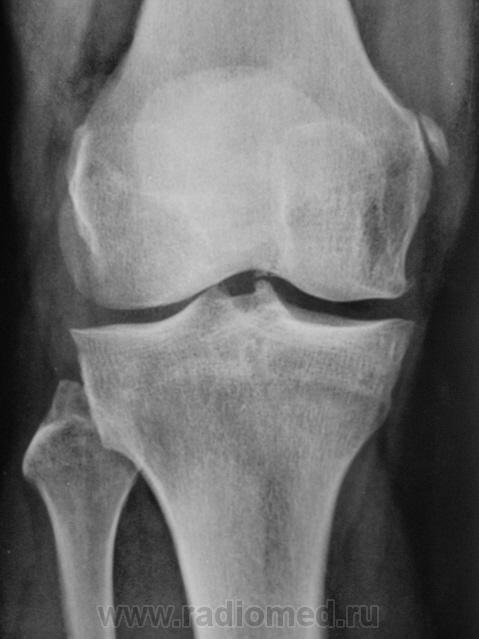

Болезнь Штида. Правосторонний гонартроз II ст. Лигаментоз крестообразных связок.

Кажется, полностью это называется "болезнь Пеллегрини-Штиды"?

Конечно, но вариантов много.